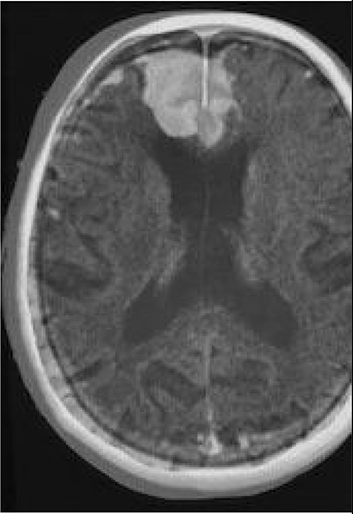

Table 6 Fused image output.

From: Multimodal medical image fusion combining saliency perception and generative adversarial network